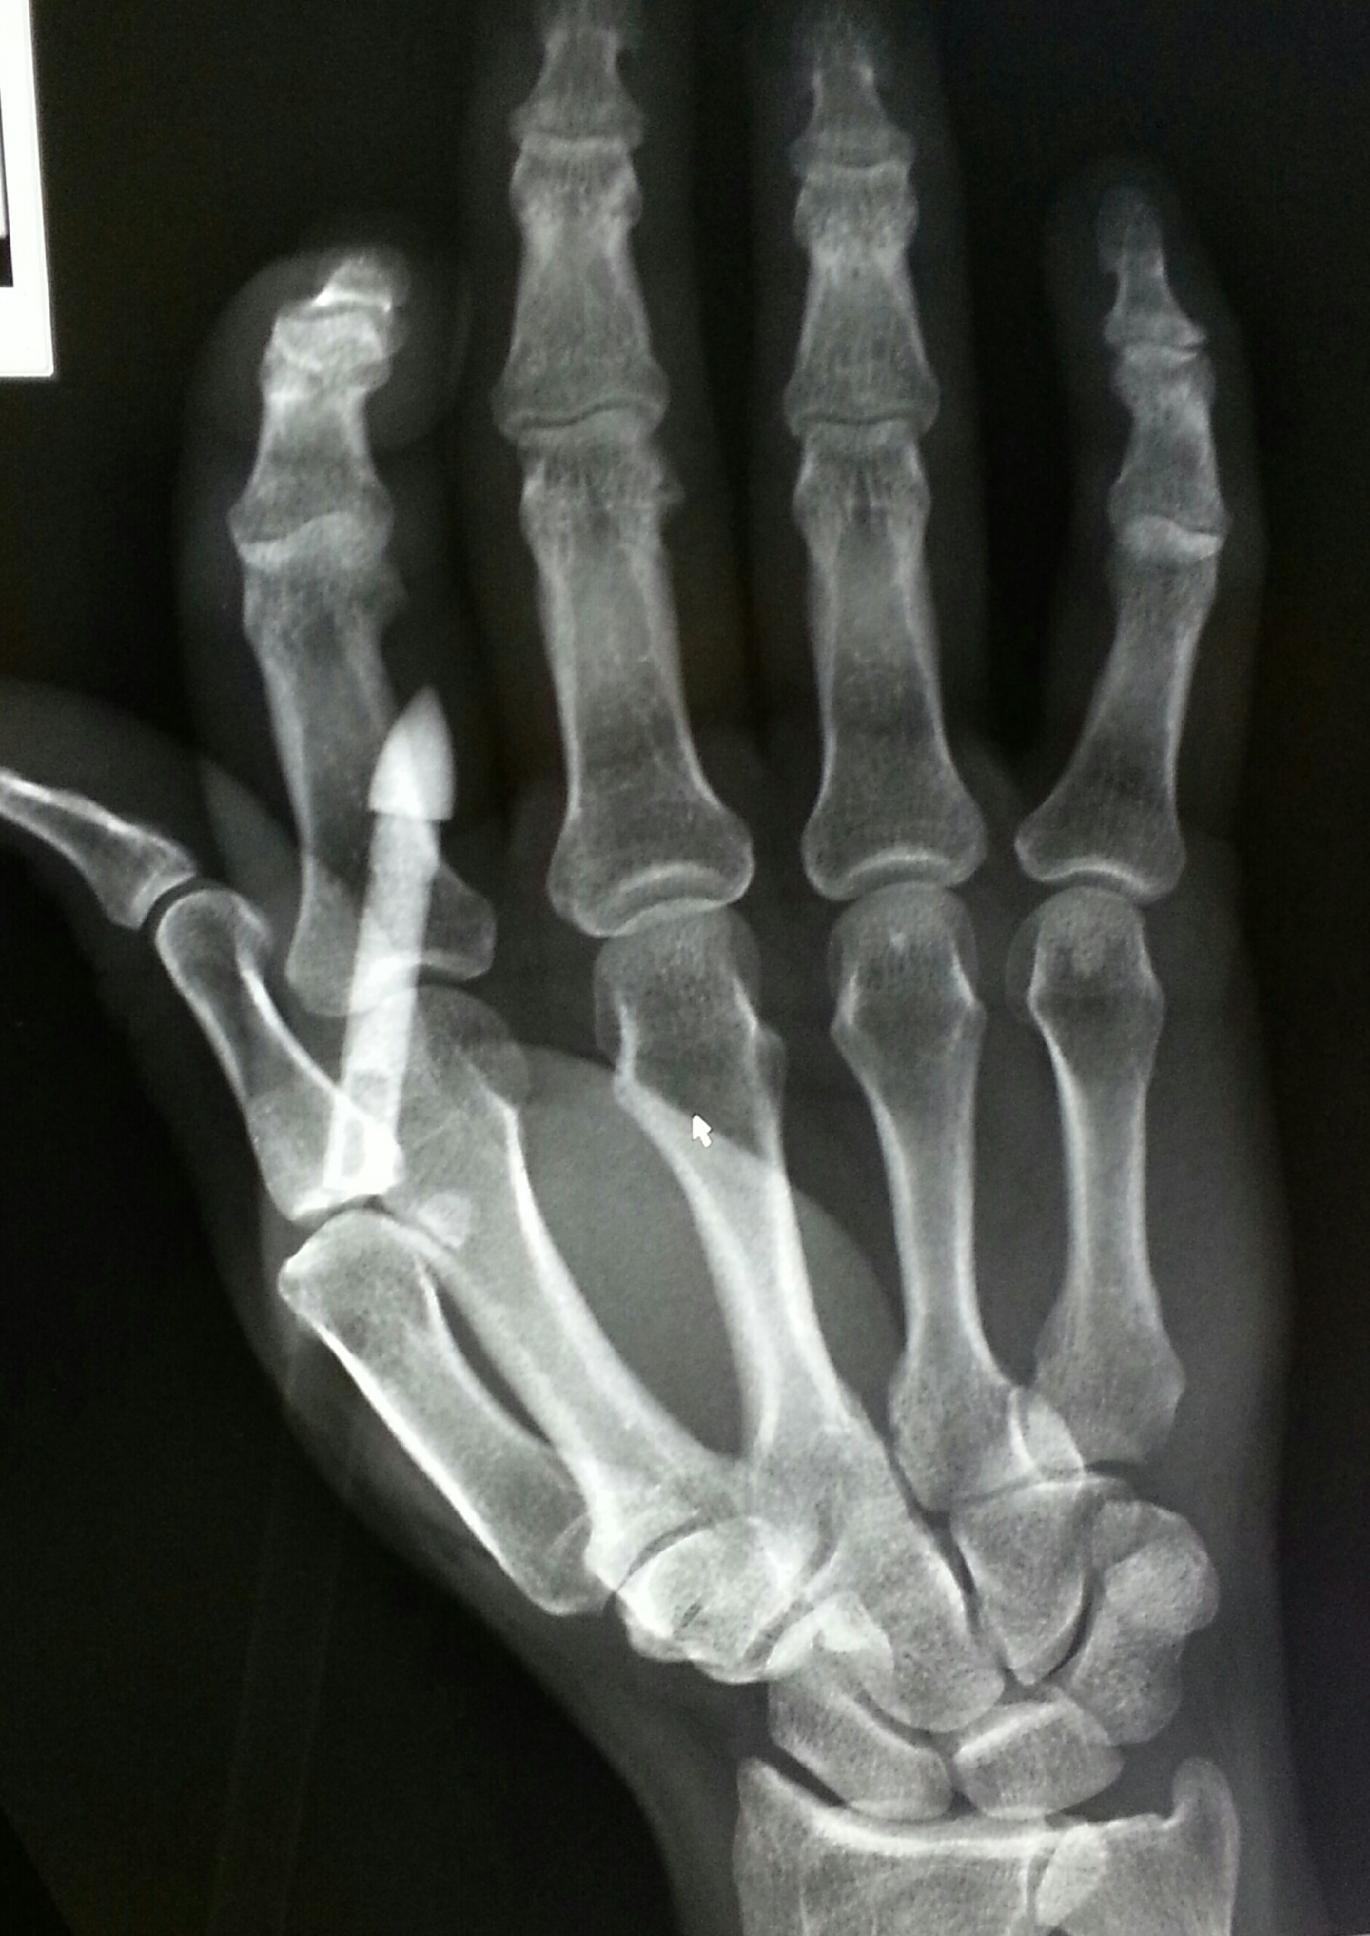

Three graphic pictures of an archery shoot gone wrong.

He’s bigger than she is of course, and so is his draw length. That means shorter arrows for her and her bow, and longer ones for him. What happens when you load an arrow in to your bow that’s shorter than it should be?

This: